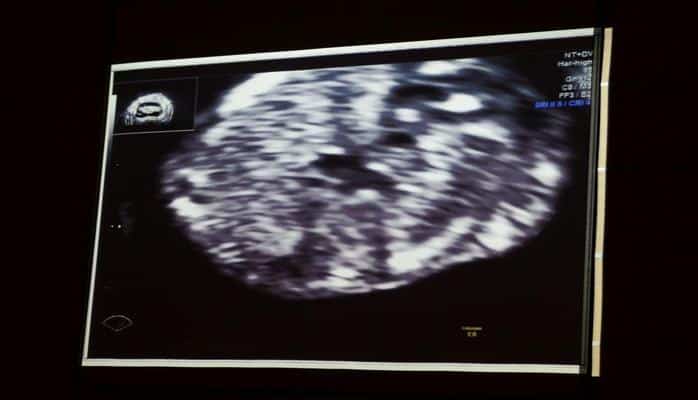

Затем состоялась монолекция радиолога Азера Фараджа.